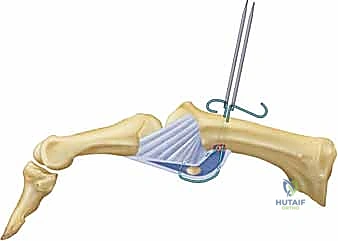

ما هي آفة ستينر (Stener Lesion)؟

تحدث هذه الحالة المعقدة عندما يتمزق الرباط الجانبي الزندي (UCL) بالكامل، وبدلاً من أن يبقى في مكانه ليلتئم، ينزلق الرباط الممزق ويصبح محاصراً فوق وتر عضلة أخرى (وتر العضلة المقربة للإبهام). هذا التداخل الميكانيكي يمنع التئام الرباط بشكل طبيعي تماماً، ويجعل التدخل الجراحي أمراً حتمياً لا مفر منه.

| طبيعة التدخل | جبيرة مخصصة (Spica)، أدوية، علاج طبيعي. | خياطة الأربطة، استخدام خطاطيف عظمية (Anchors)، إعادة بناء الأربطة. |